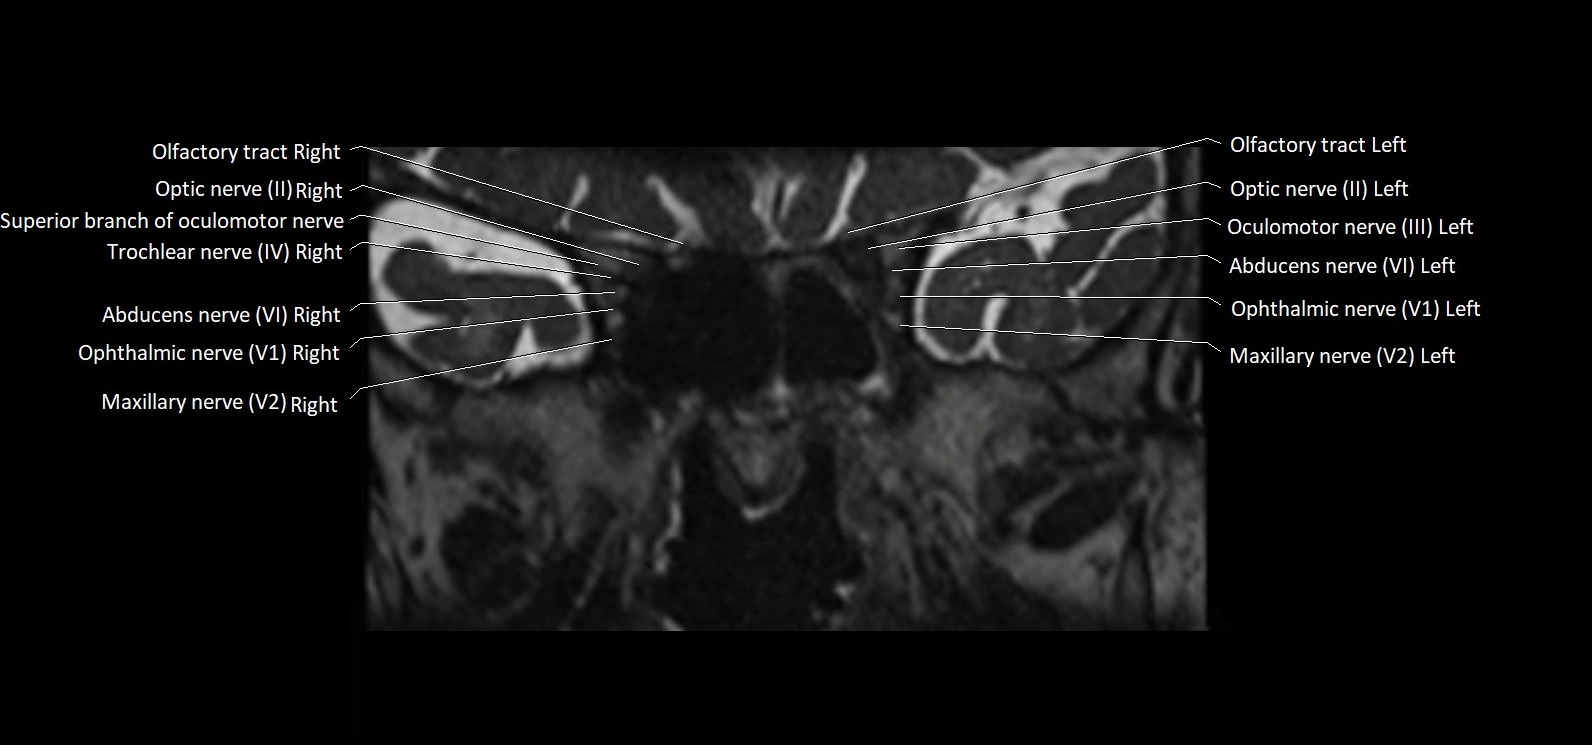

MRI Appearance

• The abducens nerve is a small, thin, linear structure

• Best visualized on high-resolution T2-weighted 3D MRI sequences (e.g., FIESTA or CISS)

• Seen as a hypointense (dark) line running from the brainstem at the pontomedullary junction, traversing the prepontine cistern, and entering Dorello’s canal under the petrosphenoidal ligament, then into the cavernous sinus, and finally the orbit

• May be challenging to visualize in standard MRI due to its small size

• Pathology may be inferred by absence, displacement, or enhancement of the nerve